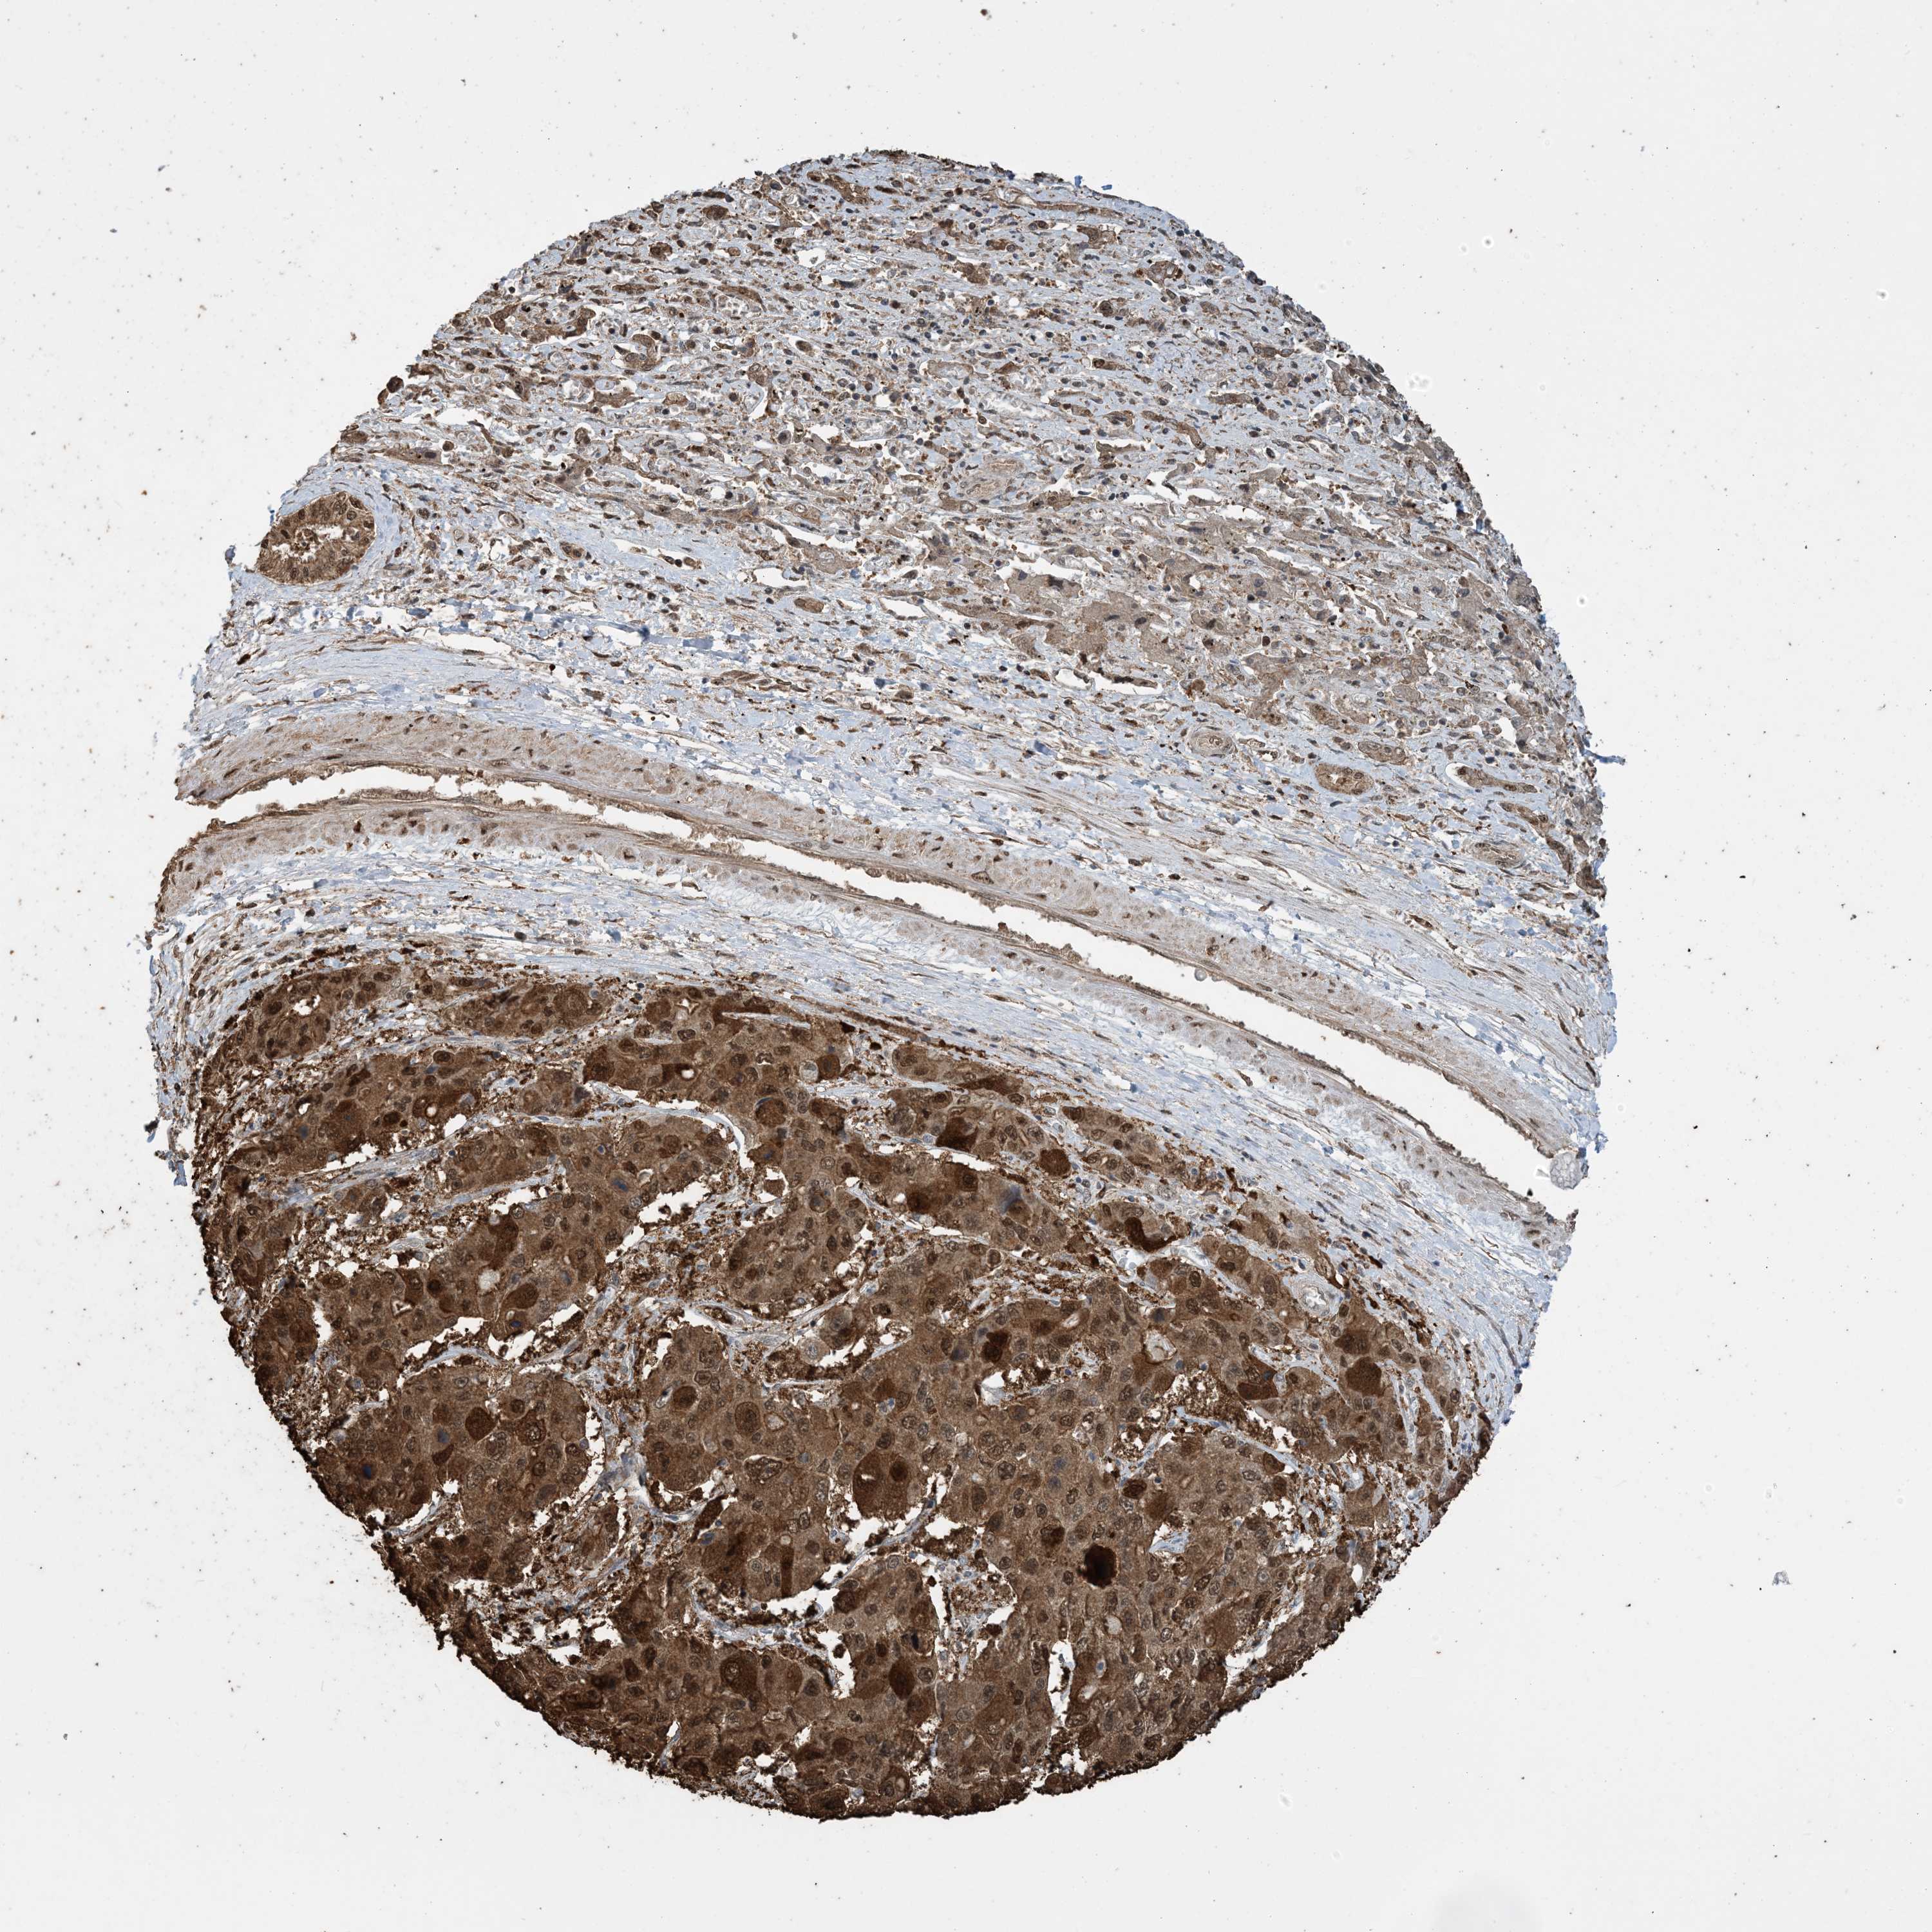

LIVER CANCER - Protein expressioni

A mouse-over function shows sample information and annotation data. Click on an image to view it in a full screen mode. Samples can be filtered based on level of antibody staining by selecting one or several of the following categories: high, medium, low and not detected. The assay and annotation is described here.

Note that samples used for immunohistochemistry by the Human Protein Atlas do not correspond to samples in the TCGA dataset.

Antibody stainingi

Antibody staining in the annotated cell types in the current human tissue is reported as not detected, low, medium, or high, based on conventional immunohistochemistry profiling in selected tissues. This score is based on the combination of the staining intensity and fraction of stained cells.

Each image is clickable and will lead to virtual microscopy that enables deeper exploration of all samples and also displays staining intensity scores, fraction scores and subcellular localization as well as patient and tissue information for each sample.

Antibody HPA052504

Antibody CAB017451

Antibody CAB032815

Staining

High

Medium

Low

Not detected

Intensity

Strong

Moderate

Weak

Negative

Quantity

>75%

75%-25%

<25%

None

Location

Nuclear

Cytoplasmic/membranous

Cytoplasmic/membranous,nuclear

Cholangiocarcinoma

Carcinoma, Hepatocellular, NOS